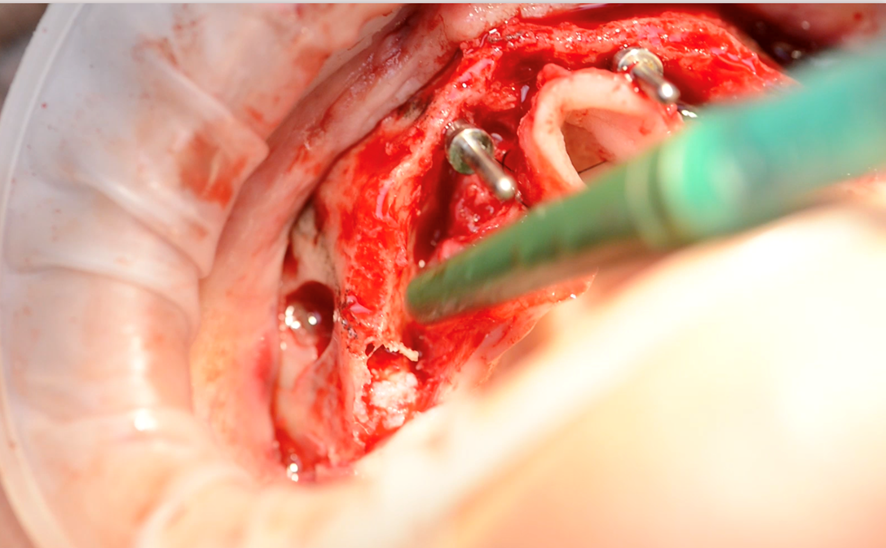

Logo após, as osteotomias transinusais foram realizadas. As fresas iniciam-se na região dos primeiros molares, atravessam a cavidade sinusal em sua porção mais anterior e ancoram seu ápice na cortical nasal. Para isso, foram selecionados dois implantes Due Cone de 3,5 mm de diâmetro por 17 mm de comprimento. Foi utilizado também o kit de fresagem convencional da Implacil de Bortoli para perfuração e instalação dos implantes anteriores e a adaptação das fresas do Kit Implaguide da mesma empresa para o preparo do leito dos implantes transinusais (Figuras 5, 6 e 7).